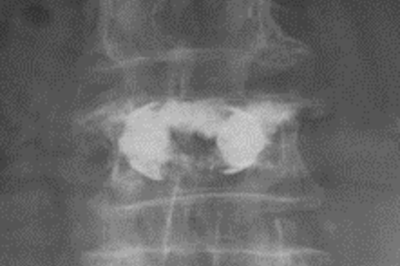

• SpineJack-Kyphoplastie

Röntgenbild einer SpineJack-Kyphoplastie.

Versorgung mit SpineJack-Kyphoplastie